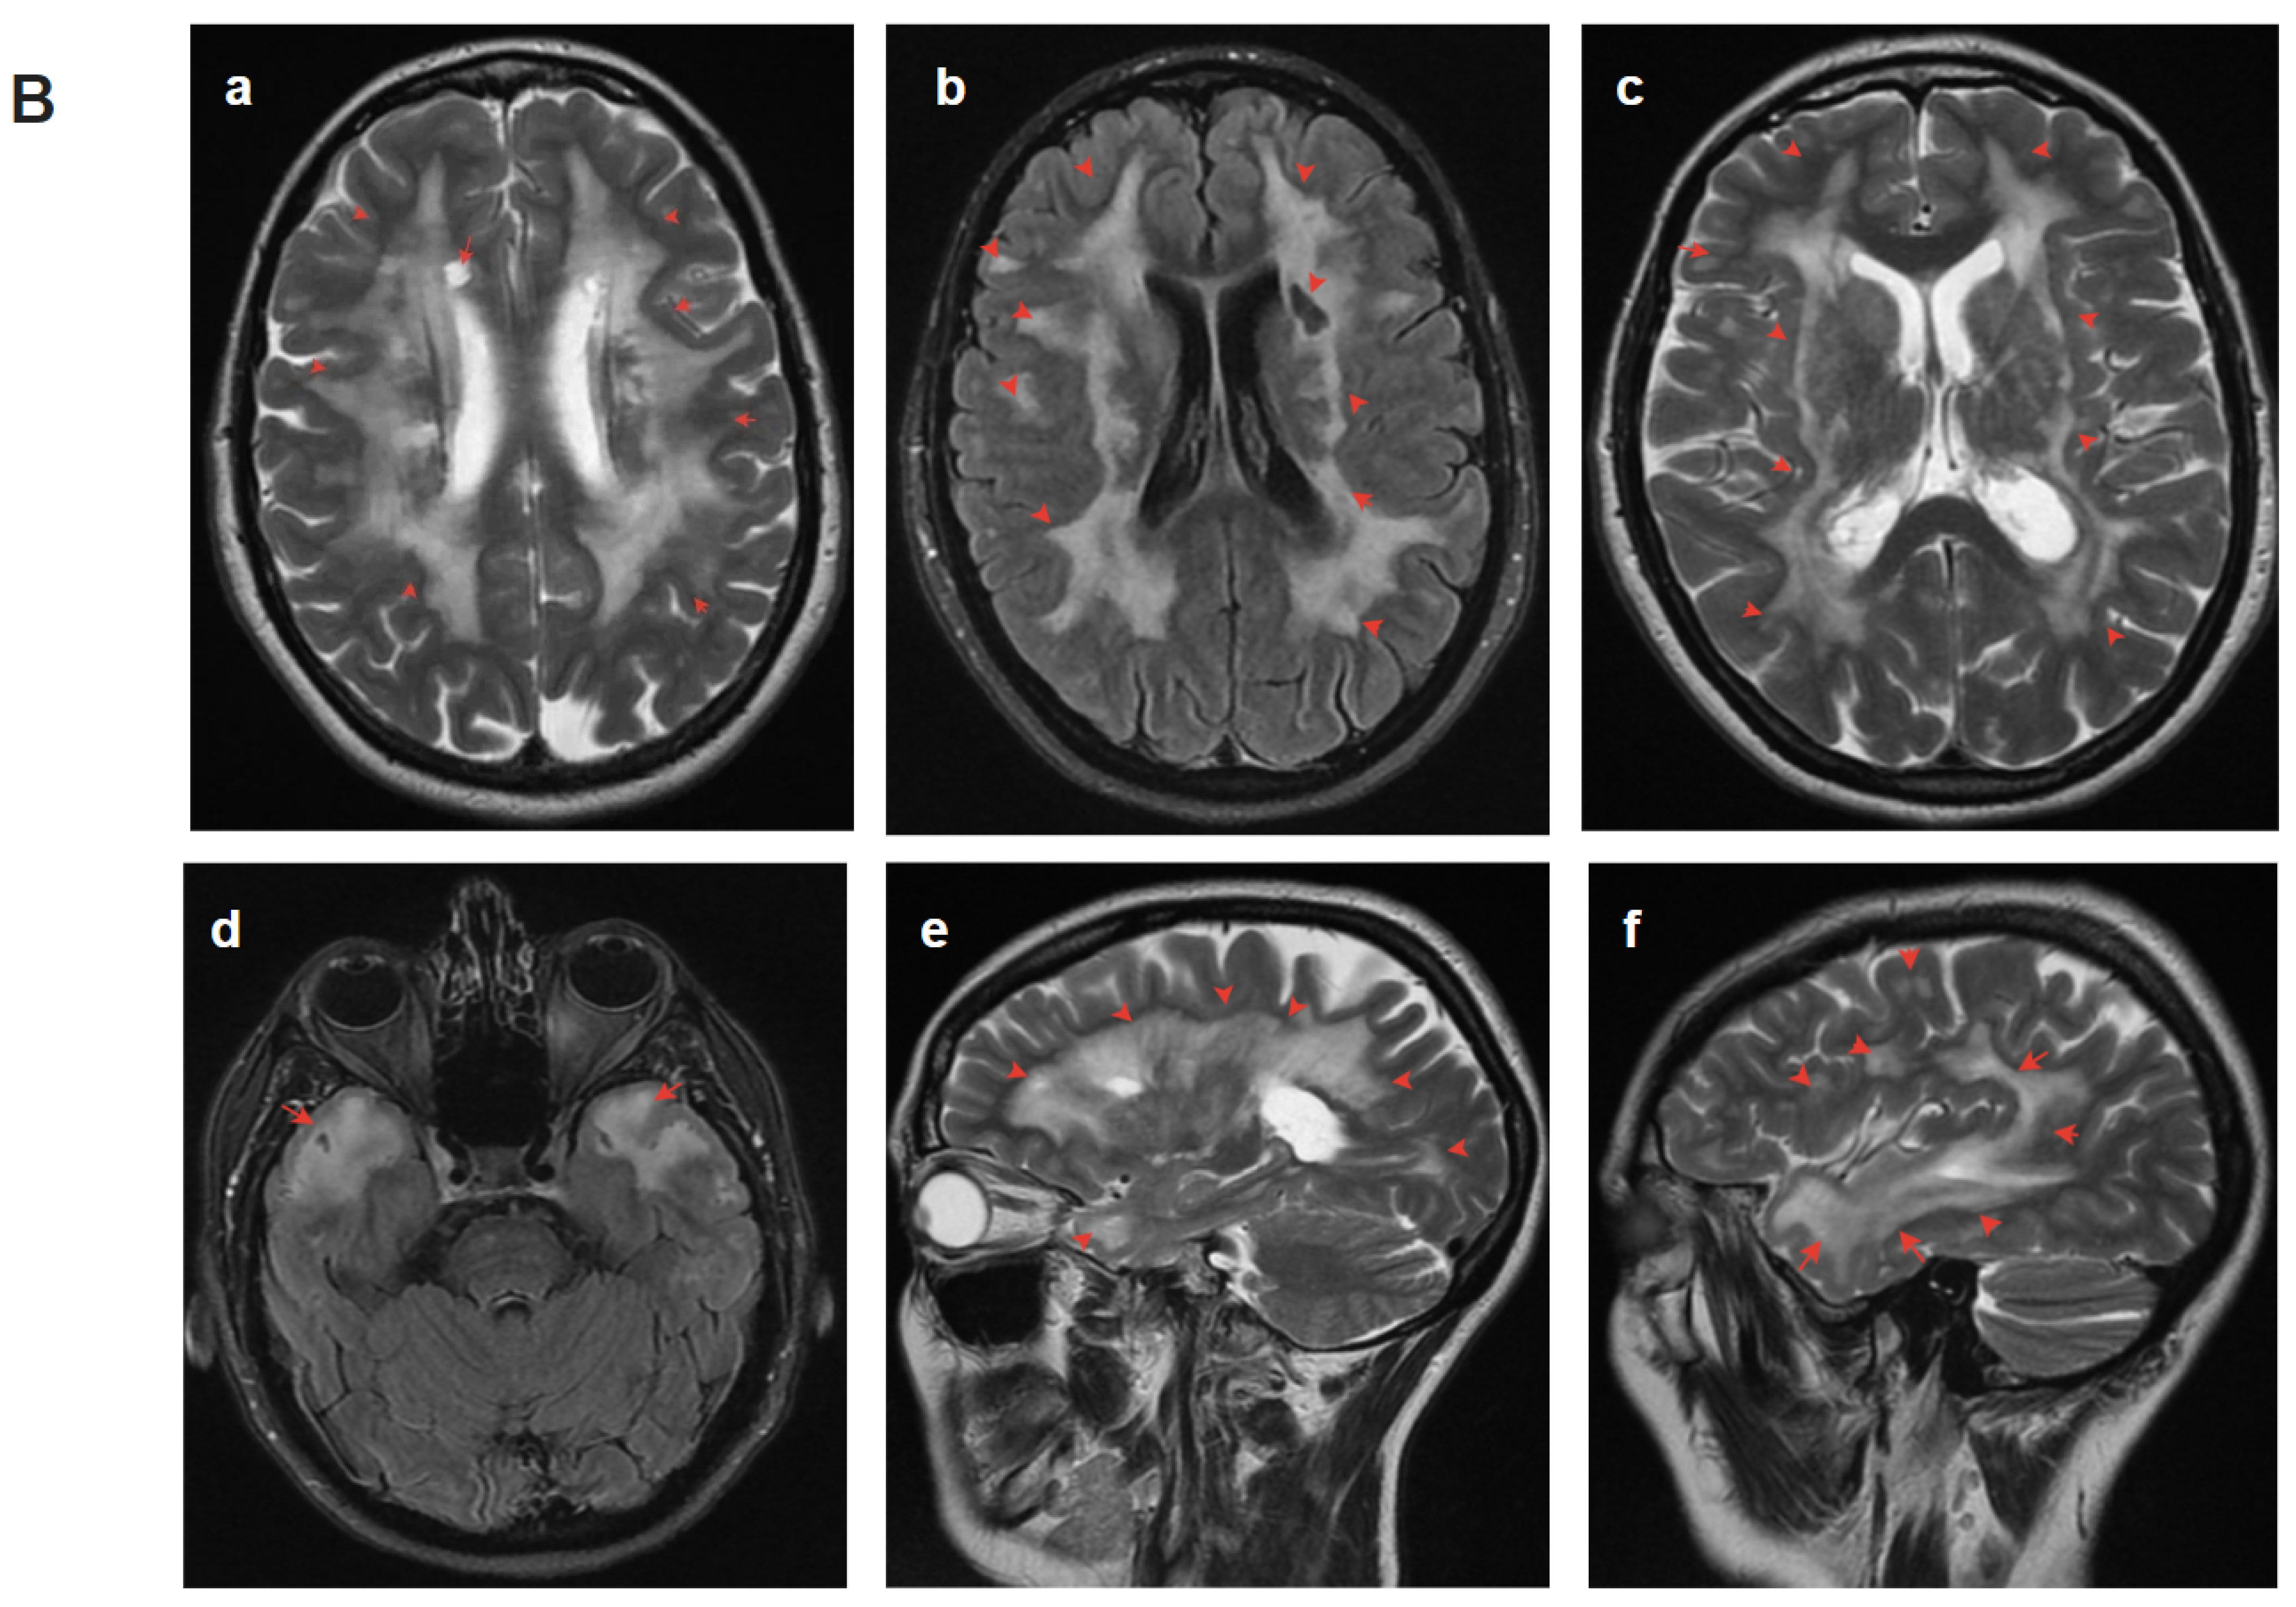

A 39-year-old woman consulted a geneticist for a diagnosis and prognosis for her offspring. Her mother (died at 69), aunt (died at 64), cousin (died at 40), grandfather (died at 47), and grandfather’s sister had an unspecified degenerative disease of the nervous system, accompanied by dementia, psychiatric disorders, and migraine (Figure 1). At age 39, the proband had an episode of slurred speech lasting 10 min. Examination by a neurologist revealed no focal neurological symptoms. Brain MRI revealed white matter hyperintensities (WHM) in the periventricular areas, which led to the suspicion of CADASIL syndrome. The c.208G>T, (p.Gly70Cys) substitution in exon 1 in the heterozygous state affecting a highly conserved protein region was identified by Sanger sequencing (Table 1). Since there were no living affected relatives, genetic testing for them was not possible. The clearly traceable autosomal dominant pattern of inheritance, debut at a young age, and similarity of clinical manifestations in relatives allowed us to confirm the diagnosis of CADASIL. The patient was referred under the care of a neurologist in the community. Within the subsequent two years, there were two more episodes of transient ischemic attack. Since the age of 43, headaches, dizziness, and memory impairment appeared. At the age of 49, an MRI of the brain revealed multiple white matter hyperintensities (WMH) lesions and multiple areas of cystic-gliosis changes; confluent areas of WMH were detected in symmetrical parts of the temporal lobes (Figure 1).

Figure 1.

Pedigree and Neuroimaging features of patient 1. (A)—Pedigree of patient 1; (B)—MRI images of the brain (IV-1), red arrows show: (a–c,e,f)—multiple white matter hyperintensities and subcortical lacunar lesions; (d)—vast, confluent areas of WMH in symmetrical parts of the temporal lobes and subcortical lacunar lesion; (e)—cerebral atrophy.

In the diagnosis of CADASIL, instrumental findings outperform clinical findings. Typical manifestations on MRI include WMH and lacunar infarcts. WMH is a common and early MRI feature of CADASIL. Increased signal intensity in the anterior temporal lobe has high sensitivity and specificity in most cases [15]. This change was detected in two of our patients (patients 1, 2). Signs of recurrent cerebral microbleeds (cortical–subcortical regions, white matter, thalamus, pons) are identified in most patients with CADASIL and are usually localized outside ischemic foci, which allows for considering it almost a pathognomonic sign of the disease [16]. These signs were also present in our patients (patients 1, 2, 3, 4.1). Symmetric periventricular WMH, commonly affecting the anterior temporal lobe, can be observed long before the first symptoms appear [17,18]. By the age of 35, essentially all patients with CADASIL have abnormal MRI findings, which occasionally may occur in the absence of clear clinical features [19,20]. A detailed study of the family history plays an important role in the diagnosis of CADASIL. As stated in patient 1, the key to the diagnosis was a family history. Some patients with a molecularly confirmed diagnosis may remain asymptomatic for a long time, even with well-defined lesions on brain MRI. Brain MRI may be normal early in the disease course, but by the fifth decade, significant white matter changes are the rule rather than the exception [21]. In a study of a cohort of 301 CADASIL patients, it was found that higher WMH associated with the temporal lobes and frontal gyri correlated with a milder course of the disease as compared with WMH in the pyramidal tracts [22]. However, the question of correlation between the degree of WMH changes and the severity of CADASIL patients remains open today and requires further study.